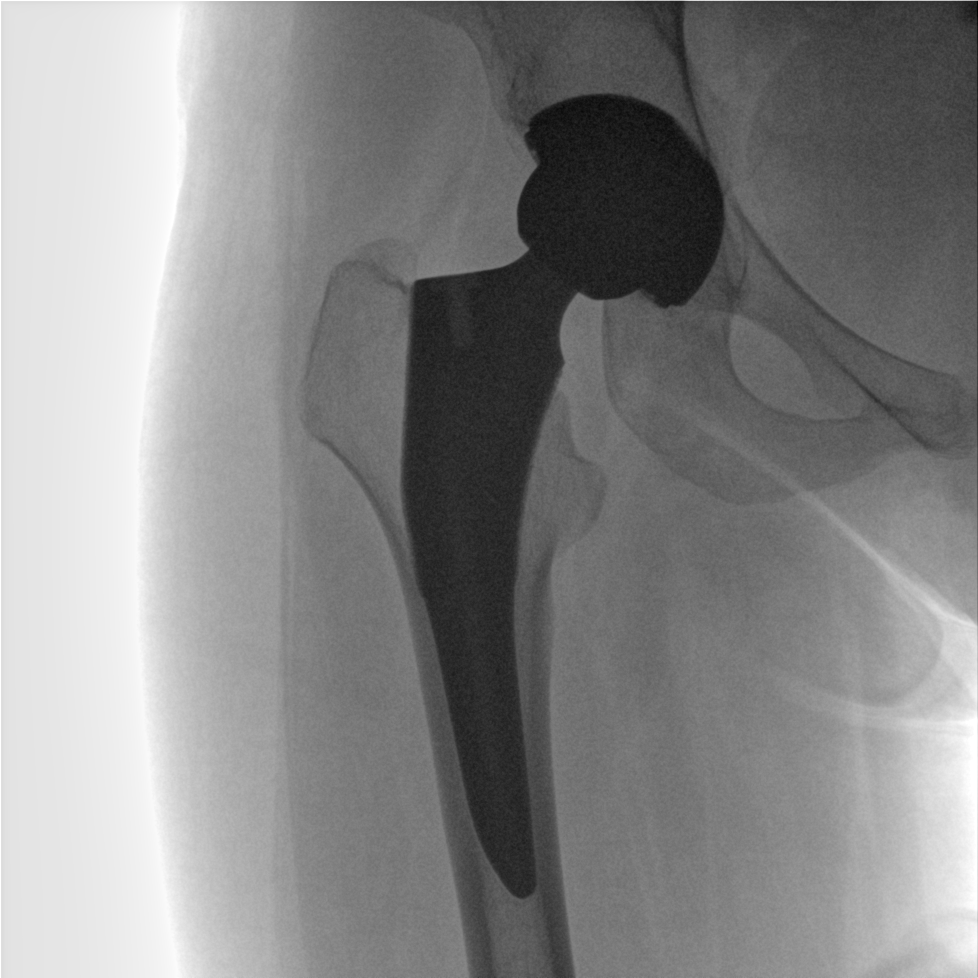

成像清晰、操作簡易、擺位便捷,主要適用于骨科、脊柱外科、矯形外科、創(chuàng)傷骨科及手術室等,能大幅度提升手術水準,降低手術風險和并發(fā)癥的概率。

術中三維成像和橫斷面圖像提供多角度的手術診斷信息,輔助醫(yī)生進行術中評估判斷,諸如骨折復位情況和內(nèi)植入螺釘?shù)某叽绾臀恢?,輔助手術更好地完成。

提供更大的術中三維成像視野,采集更多圖像信息,可一次拍全全段頸椎、全段腰椎、七節(jié)胸椎、雙側(cè)骶髂關節(jié)、股骨頭及單側(cè)盆骨。